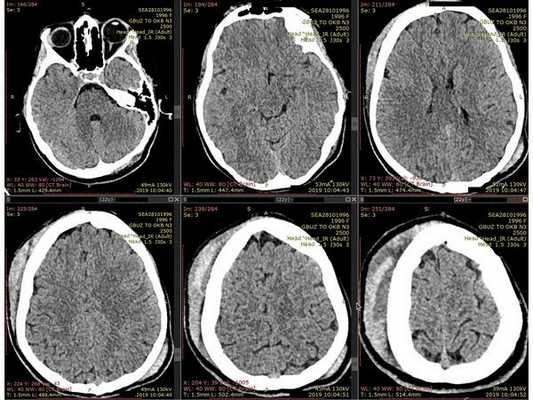

- Компьютерная томография головного мозга: травматической патологии не выявлено; определяется обширная гематома мягких тканей в правой лобно-височно-теменной области.

- Компьютерная томография шейного отдела позвоночника: выявлен компрессионно-оскольчатый перелом тела 6-го шейного позвонка (С6) и его дуги справа.